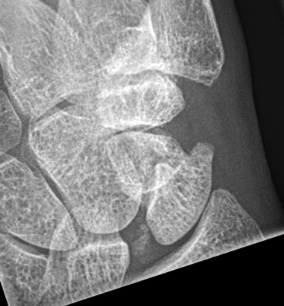

X-ray

5 images

- PA / lateral

- PA in 45° oblique pronation / PA 45o oblique supination

- PA in ulna deviation

Scaphoid waist fracture 1 mm displaced

Scaphoid fracture with significant displacement

Scaphoid proximal pole fracture